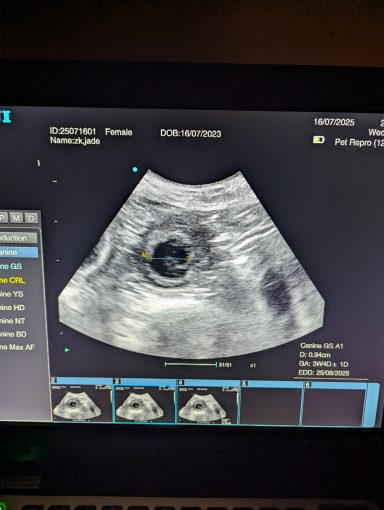

Pregnancy ultrasound scanning - Our pregnancy ultrasound service provides safe, non-invasive confirmation of pregnancy in both dogs and cats. Using advanced scanning technology and gentle handling techniques, we deliver clear, reliable results while prioritizing your pet’s comfort and wellbeing.Whether you visit our calm, home-based clinic or book a mobile appointment, we tailor each session to suit your pet’s needs—supporting responsible breeding with compassion, precision, and care.

Ultrasound pregnancy scanning is a safe, non-invasive way to confirm pregnancy in dogs and cats, offering breeders and pet owners peace of mind and vital information to support responsible care. It allows us to detect gestational sacs, assess foetal development, and estimate litter size—all while ensuring the wellbeing of the animal.

Pregnancy can sometimes be detected as early as Day 18 post-mating, but scanning at this stage is not routinely recommended. Embryos are still developing and may not be clearly visible, and there is a natural risk of embryo resorption, which can lead to misleading or inconclusive results.

For the most accurate and reliable scan, we advise booking between Day 25 and Day 32, when pregnancy is more easily confirmed and foetal structures are clearer. If an early scan is performed and no pregnancy is detected, we offer a FREE complimentary re-scan after 7 days at the clinic to ensure clarity and support informed decision-making.

Our approach balances early insight with ethical care—always prioritizing the comfort of the animal and the accuracy of the results.